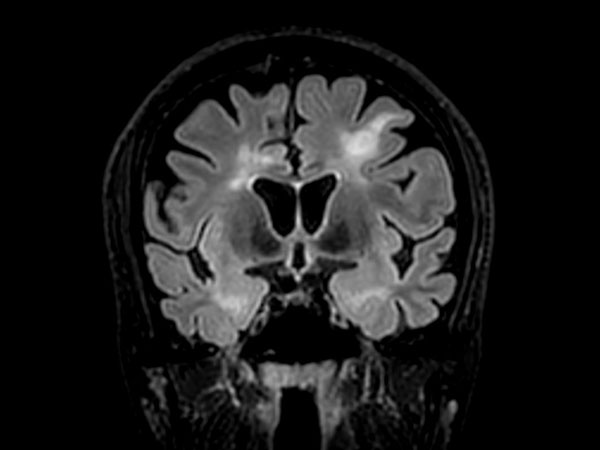

3D T2w FLAIR BrainVIEW Compressed SENSE

3D T2w FLAIR BrainVIEW (reformat) Compressed SENSE